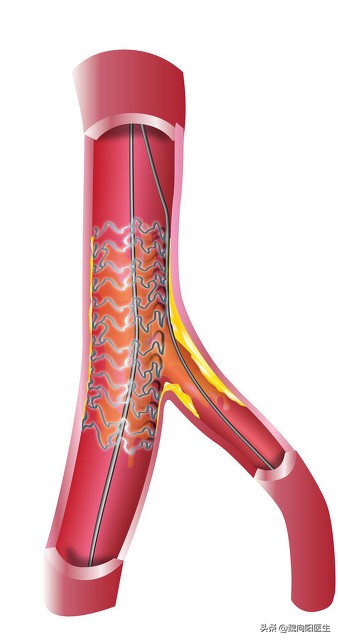

立即给球囊扩张+支架植入,患者狭窄消失,远端血流通畅,大脑重新恢复供血。